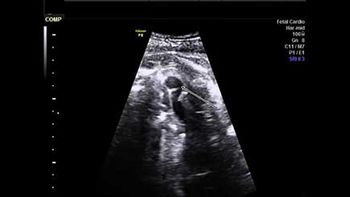

Challenge your diagnostic skills: Is this fetal heart normal or abnormal?